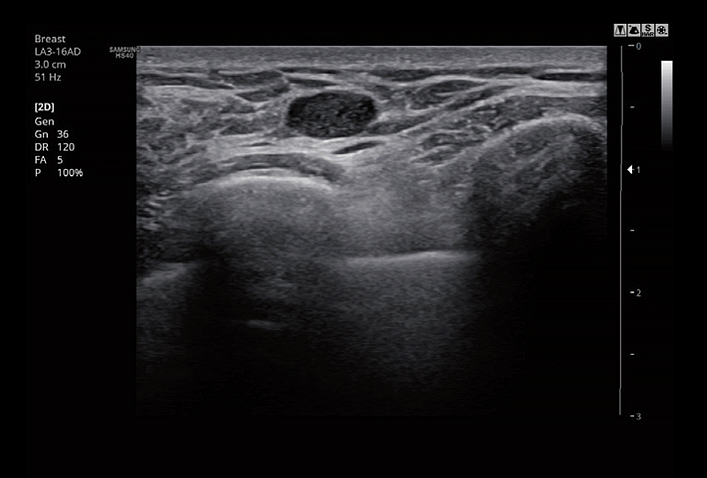

The feature, which analyzes selected lesions in the breast ultrasound study and shows the analysis data, applies BI-RADS ATLAS* (Breast Imaging-Reporting and Data System, Atlas) to provide standardized reporting; and helps diagnosis with the streamlined workflow.

LA3-16ADApplication:Small parts, Vascular, Musculoskeletal, Abdomen, Obstetrics, Gynecology, Pediatric, Emergency |